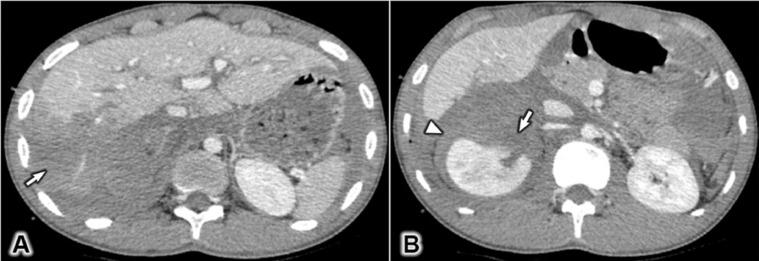

Gastric injury due to trauma is a rare complication that occurs in approximately 0.04%-1.2% of all instances of abdominal trauma. When imaging trauma cases, certain areas can be obscured by several inevitable reasons. Despite its rarity, the high mortality rate of a gastric injury requires an early and accurate diagnosis. We present the case of an 18-year-old male who suffered a gastric rupture of the greater curvature following a road traffic collision before providing a brief review of the literature.